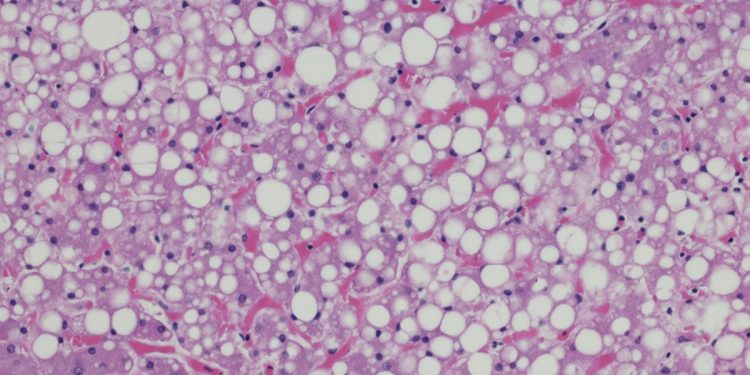

Cada vez mais comum entre os brasileiros, a esteatose hepática, conhecida popularmente como gordura no fígado, é uma condição muitas vezes silenciosa, mas que pode causar problemas sérios.

O quadro, que está relacionado à obesidade, sedentarismo e resistência à insulina, é caracterizado pelo acúmulo de células de gordura no tecido do fígado.

“O problema começa de forma discreta, mas pode evoluir para inflamações crônicas e fibrose, aumentando o risco de cirrose e câncer de fígado”, explica o endocrinologista Paulo Bittencourt, presidente do Instituto Brasileiro do Fígado (Ibrafig).

Sintomas da gordura no fígado

• Cansaço frequente e sensação de fraqueza.

• Desconforto ou dor leve no lado direito do abdômen.

• Enjoo e perda de apetite.

• Inchaço abdominal.

• Alterações nos exames de sangue, com aumento das enzimas hepáticas.